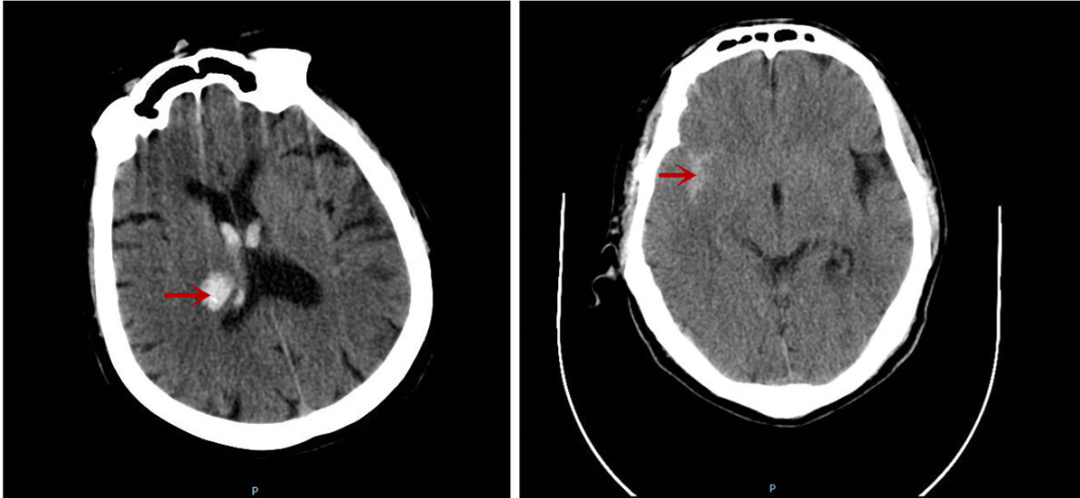

據(jù)悉,這兩位患者在送醫(yī)時分別呈現(xiàn)突發(fā)頭痛伴頭暈、突發(fā)肢體活動障礙等癥狀,經(jīng)急診顱腦CT檢查,一位確診為丘腦出血,另一位為蛛網(wǎng)膜下腔出血。

圖中所示分別為丘腦出血及蛛網(wǎng)膜下腔出血情況